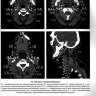

Примеры страниц из книги "Визуализация заболеваний шеи" - Труфанов Г. Е., Припорова Ю. Н.